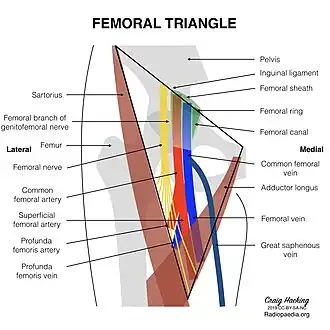

Femoral triangle showing included blood vessels and nerves | |

The femoral triangle is bounded:[2]

- superiorly (also known as the base) by the inguinal ligament.[2]

- medially by the medial border of the adductor longus muscle. (Some people consider the femoral triangle to be smaller hence the medial border being at the lateral border of the adductor longus muscle.)[2]

- laterally by the medial border of the sartorius muscle.[2]

The apex of the triangle is continuous with the adductor canal.[2] The roof is formed by the skin, superficial fascia, and deep fascia (fascia lata). The superficial fascia contains the superficial inguinal lymph nodes, femoral branch of the genitofemoral nerve, branches of the ilioinguinal nerve, superficial branches of the femoral artery with accompanying veins, and upper part of the great saphenous vein. The deep fascia has a saphenous opening and the opening is covered by the cribiform fascia.[2]

Its floor is formed by the pectineus and adductor longus muscles medially and iliacus and psoas major muscle laterally.[2]

Contents

The femoral triangle is important as a number of vital structures pass through it, right under the skin. The following structures are contained within the femoral triangle (from lateral to medial):

- Lateral cutaneous nerve of thigh - It crosses the lateral angle of the triangle, runs on the lateral side of the thigh and ends by dividing into anterior and posterior branches. The anterior branch supplies the anterolateral aspect of the thigh while the lateral branch supplies the lateral aspect of the gluteal region.[2]

- Femoral nerve and its terminal branches - The nerve enters the femoral triangle by passing beneath the inguinal ligament, just lateral to the femoral artery. In the thigh, the nerve lies in a groove between iliacus muscle and psoas major muscles, outside the femoral sheath, and lateral to the femoral artery. After a short course of about 4 cm in the thigh, the nerve is divided into anterior and posterior divisions, separated by lateral femoral circumflex artery.[2]

- Nerve to pectineus - This nerve arises from the femoral nerve just above the inguinal ligament. It passes behind the femoral sheath to reach the anterior surface of the pectineus muscle.[2]

Femoral sheath encloses the upper 4 cm of the femoral vessels. Its contents are shown below (from lateral to medial):

- Femoral branch of the genitofemoral nerve - occupies the lateral compartment of the femoral sheath along with femoral artery. It supplies the skin over the femoral triangle.[2]

- Femoral artery and its branches - It emerges from the base of the femoral triangle at the mid-inguinal point (midpoint between the anterior superior iliac spine and the pubic symphysis of the pelvic bone) and exits through the apex of the triangle into the adductor canal.[2]

- Femoral vein and its tributaries - The vein lies medial to the femoral artery at the base of the triangle but as it approaches the apex of the triangle, it lies posteromedially to the femoral artery. It receives drainage from great saphenous vein, circumflex veins, and veins corresponding to the branches of the femoral artery here.[2]

- Deep inguinal lymph nodes - It lies deep to the deep fascia, medial to the upper part of the femoral vein, inside the femoral canal (medial compartment of the femoral sheath). Cloquet's node (also known as Rosenmuller's node) also lies in this canal. It receives lymphatic drainage from superficial inguinal lymph nodes, lymphatic drainage from the glans penis or clitoris, and from the deep lymphatics of the lower limb.[2]